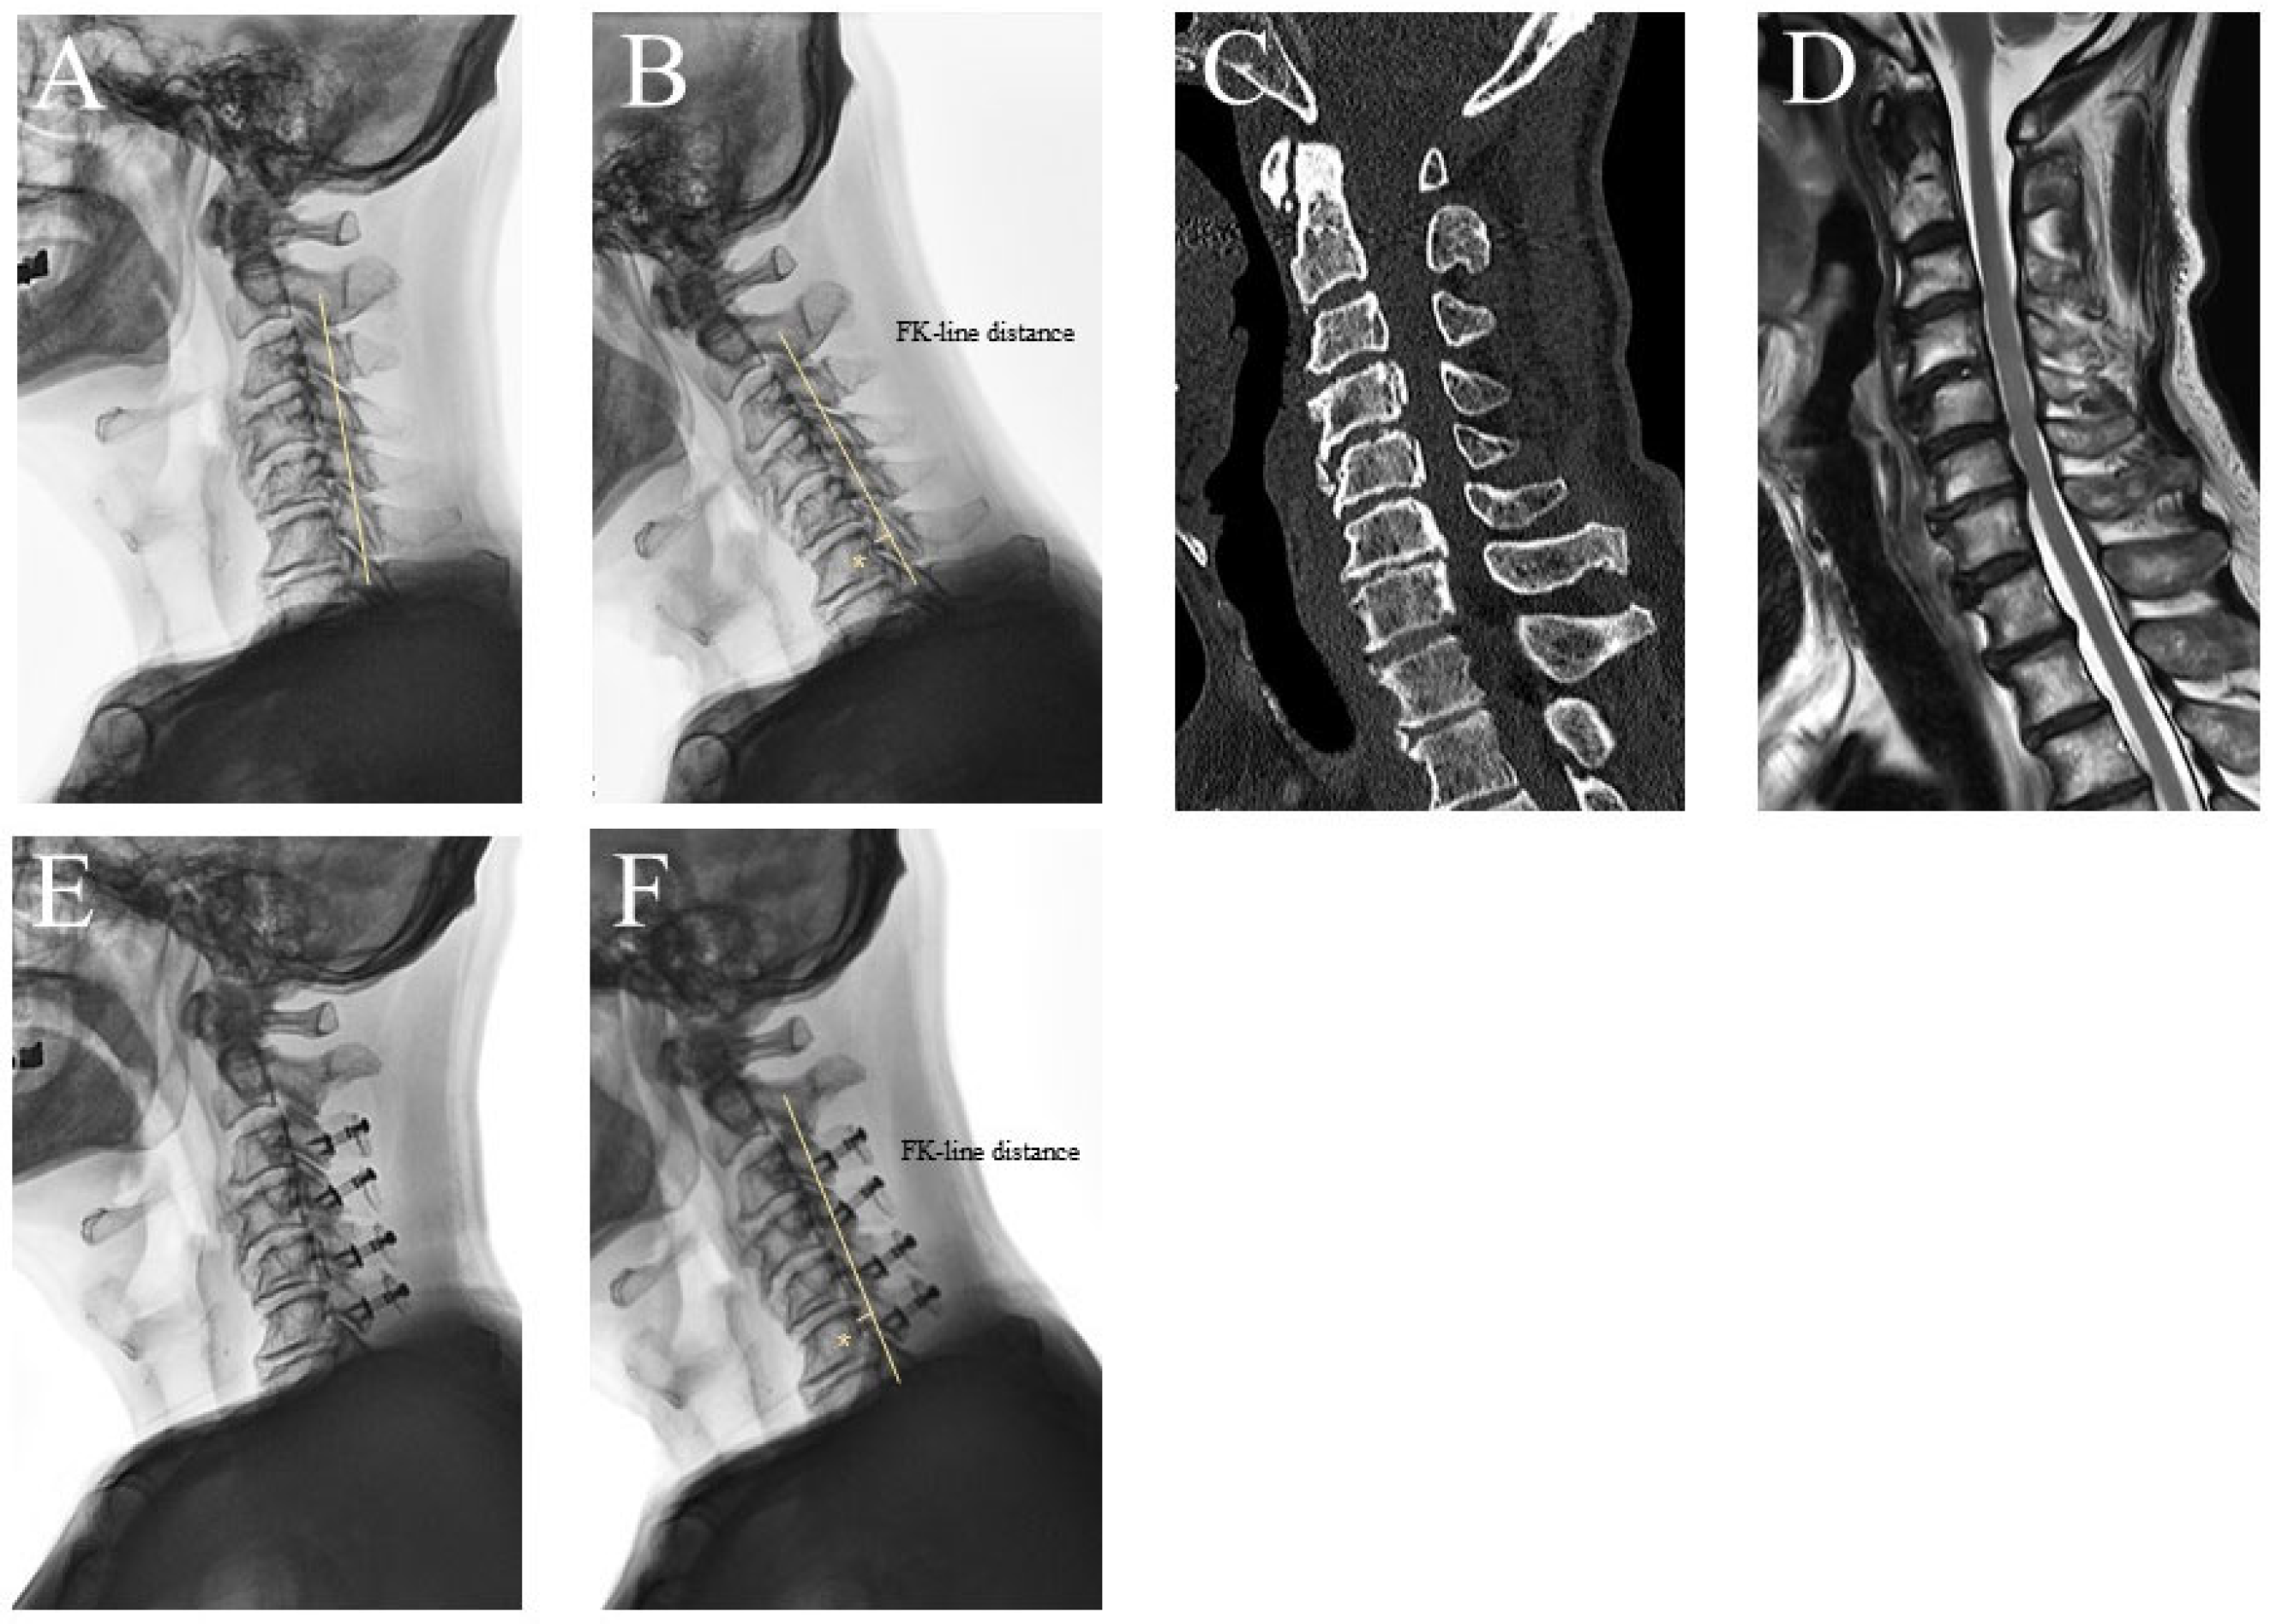

2.1. Radiologic Evaluation

| FKD | FK-line distance |

- Miyazaki, M.; Ishihara, T.; Kanezaki, S.; Hirakawa, M.; Iwasaki, T.; Abe, T.; Tsumura, H. Relationship between K-line distance and surgical outcome in cases of laminoplasty for cervical ossification of the posterior longitudinal ligament. Medicine 2022, 101, e31605. [Google Scholar] [CrossRef]